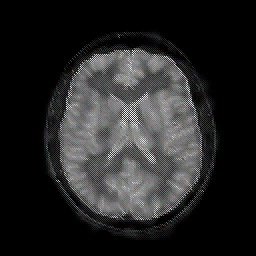

Tour 1: Next/Previous/Start: These images show typical findings in AIDS dementia: patchy hypoperfusion with a multifocal distribution which tends to be seen prominently in the frontal lobes. Compare with normal. Defects in cerebral perfusion have been previously reported in HIV positive individuals by single photon emission computed tomography (SPECT)[Masdeu, 1989 ][Pascal, 1991 ][Pohl, 1988 ][Holman, 1992 ][Schielke, 1990]. The anatomic and clinical significance of these findings, however, has remained uncertain. Because previous studies have shown that AIDS dementia complex (ADC) is associated with both functional defects and structural evidence of brain volume loss, we spatially matched (registered) the functional and structural data to assess the extent to which observed perfusion defects were "real", that is, represented low tracer uptake from structurally normal brain. The image datasets shown here are sampled along the same plane of view, to permit the direct comparison of SPECT and MR images in ADC. This type of analysis shows that there are functional defects (ie perfusion defects) in areas that appear non-atrophic. These are perhaps sites of early damage in which the structural images are still relatively normal.